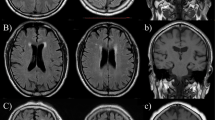

T1-weighted anatomical images were segmented into gray (GM) and white matter (WM) regions of interest using the multi-atlas, multi-warp segmentation (MUSE) tool32, which uses an ensemble of diverse brain atlases and is relatively robust to MRI scanner and protocol variations. Regional volumes from the multi-site studies were harmonized using ComBat-GAM8. This technique corrects for systematic variations in brain volumes caused by differences in scanning equipment—such as the manufacturer and model of the scanner, the magnetic field strength, the hardware and sequences used—while ensuring that inherent biological differences among individuals, such as age, gender, and brain size, are preserved. DeepMRSeg, a deep-learning-based segmentation tool, was used to derive total intracranial volumes (ICV) from T1-weighted images and WMH fluid-attenuated inversion recovery (FLAIR) and/or T2-weighted images33. WMH volumes were summarized within the lobar and deep WM regions. Raw images and segmentation masks underwent a previously established two-step semi-automated quality control procedure34, available as a standalone software package MRISnapshot (https://cbica.github.io/MRISnapshot/). The procedure automatically ranked scans based on a quality score derived from segmented ROI volumes and flagged segmentations that deviated most from expected volume distributions. Flagged segmentations were visually inspected using visualization reports created by MRISnapshot to identify and exclude poor-quality segmentations. All regional volume measures of GM, WM, and WMH were adjusted for age, sex, and ICV, and the residuals were standardized to zero-mean and unit-variance for the ML models. See Supplementary Information S2 for a list of imaging features and an illustration of harmonization outcomes.

Cardiovascular and metabolic risk factors (CVMs) contribute to distinct alterations in brain structure, potentially leading to diverse patterns of brain change. The current study leverages supervised machine learning (ML) to derive the phenotypic expression of CVMs from structural brain magnetic resonance images (sMRI). T1-weighted and T2-weighted FLAIR MRI from the multi-study iSTAGING dataset underwent rigorous preprocessing, segmentation, quality control (QC), and harmonization across study sites to obtain region of interest (ROI) brain volumes and white matter hyperintensity (WMH) volumes, respectively. These imaging features serve as inputs to the ML models. To establish ground truth labels for the ML models, clinical measurements, laboratory tests, and self-reported medical history were standardized to determine the presence or absence of five key CVMs: hypertension, hyperlipidemia, smoking, obesity, and type 2 diabetes mellitus. The ML models identify distinct Spatial Patterns of Abnormalities on sMRI associated with each CVM, summarized as individualized phenotypic expression scores (SPARE-CVMs), reflecting the influence of individual CVMs on brain structure.